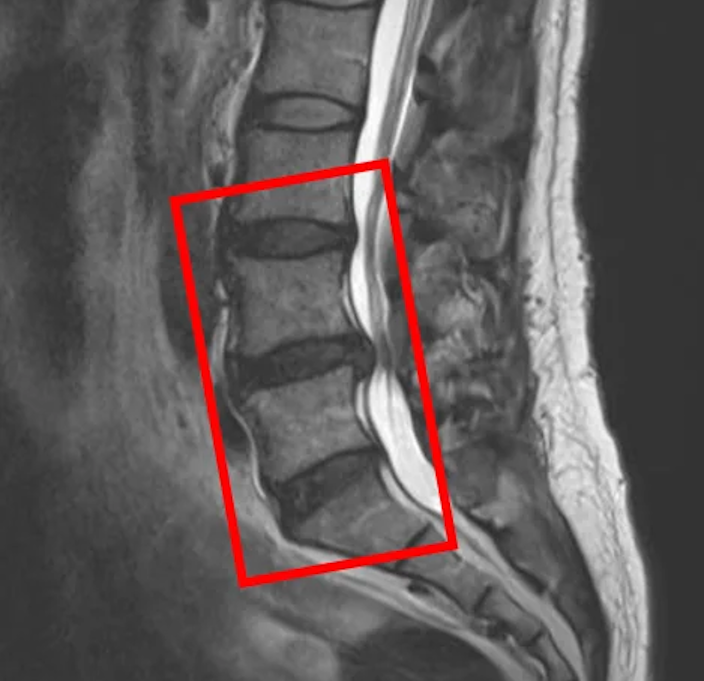

По данным МРТ и результатам осмотра пациента выявлены грыжи межпозвоночных дисков L3/L4, L4/L5, L5/S1, а также стеноз межпозвонковых отверстий на уровне диска L4/L5.

В клинике проведена селлгель-терапия на 3 межпозвоночных дисках (L3/L4, L4/L5, L5/S1).